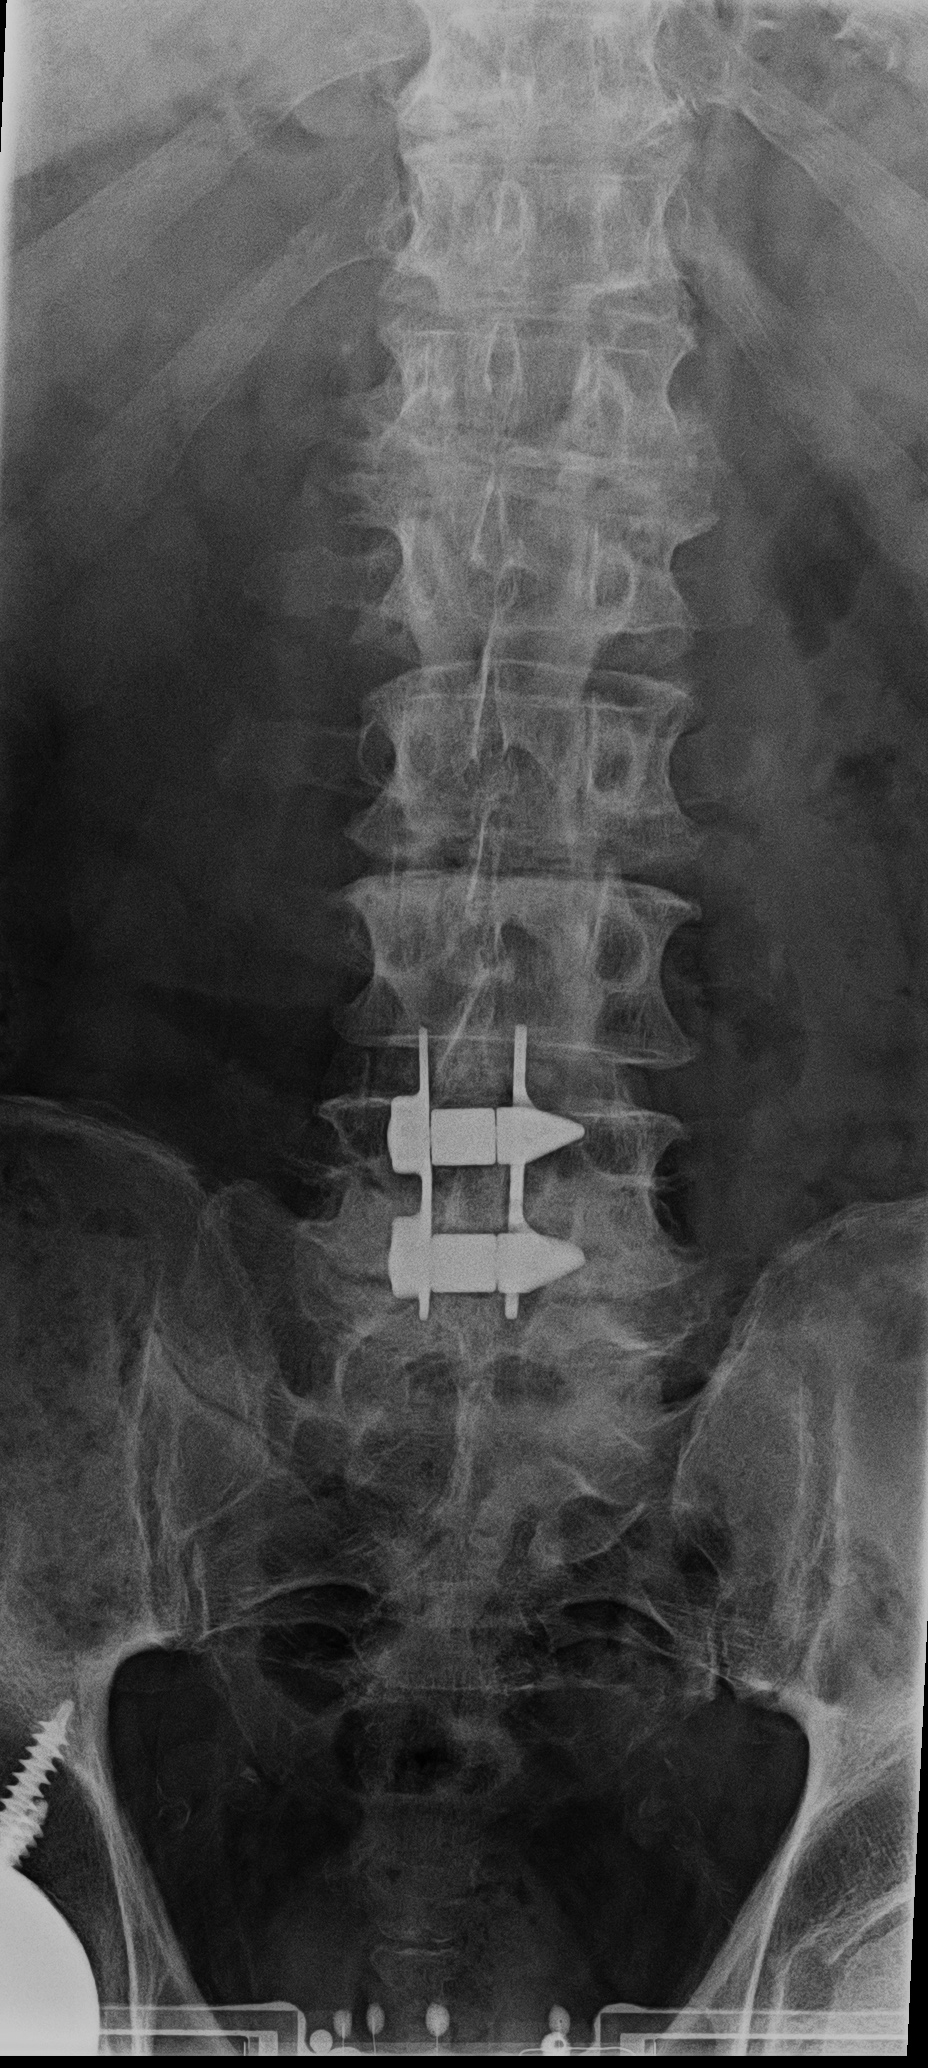

| Zero-Profile lumbar fixation L2-L5 |

| 45 year-old woman with L2-5 anterior lumbar interbody fusion (ALIF) for low back pain. The lateral views are respectively in neutral and flexion positions. The CT images are selected slices in the coronal and sagittal planes, respectively. |

| Zero-Profile lumbar fixation L2-L4 |

| 45 year-old woman with L2-5 anterior lumbar interbody fusion (ALIF) for low back pain. |